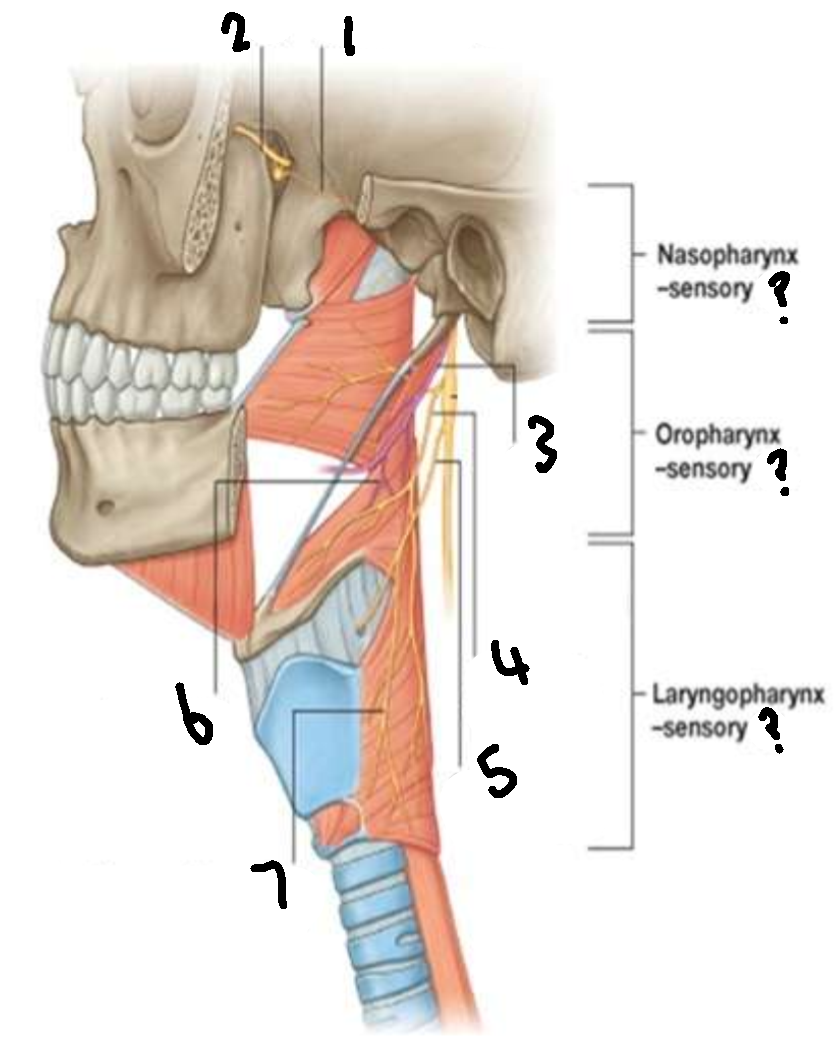

What provides sensory innervation to the nasopharynx?

mandibular branch of trigeminal V2

What provides sensory innervation to the oropharynx?

glossopharyngeal IX

What provides sensory innervation to the laryngopharynx?

vagus X

What is 1?

pharyngeal branch of V2

What is 2?

maxillary branch of trigeminal V2

What is 3?

glossopharyngeal IX

What is 4?

pharyngeal branch of vagus X

What is 5?

superior laryngeal nerve

What is 6?

pharyngeal branch of IX

What is 7?

external laryngeal branch of superior laryngeal nerve of X